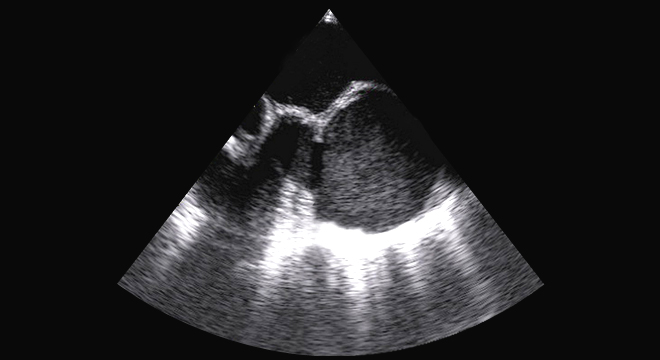

Herzklappenfehler: Echokardiographie (Ultraschall)

• Echokardiographie (Ultraschall) mit oder ohne Kontrastfarbe (beste Untersuchung zur Diagnose einer Klappenerkrankung): damit werden die Herzbewegung und die Funktion der einzelnen Kammern farbig dargestellt